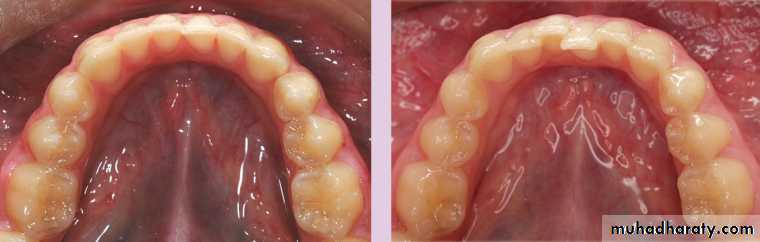

The dentition does not remain static throughout life. Crowding of the mandibular incisors is one of the most common problems encountered in the permanent dentition and lower incisor alignment is one of the most likely things to relapse after orthodontic treatment.Studies of untreated subjects followed from the mixed dentition into adulthood have shown a tendency for the width and length of the mandibular arch to decrease and for crowding of the anterior teeth to increase .

Primary crowding refers to a discrepancy of tooth dimension and jaw size, mainly determined genetically. Secondary crowding is caused by environmental factors, including local space conditions in the dental arches and the position and function of the tongue, the lips and the buccal musculature. Tertiary crowding occurs during adolescence and post-adolescence with a predilection for the lower labial segment.